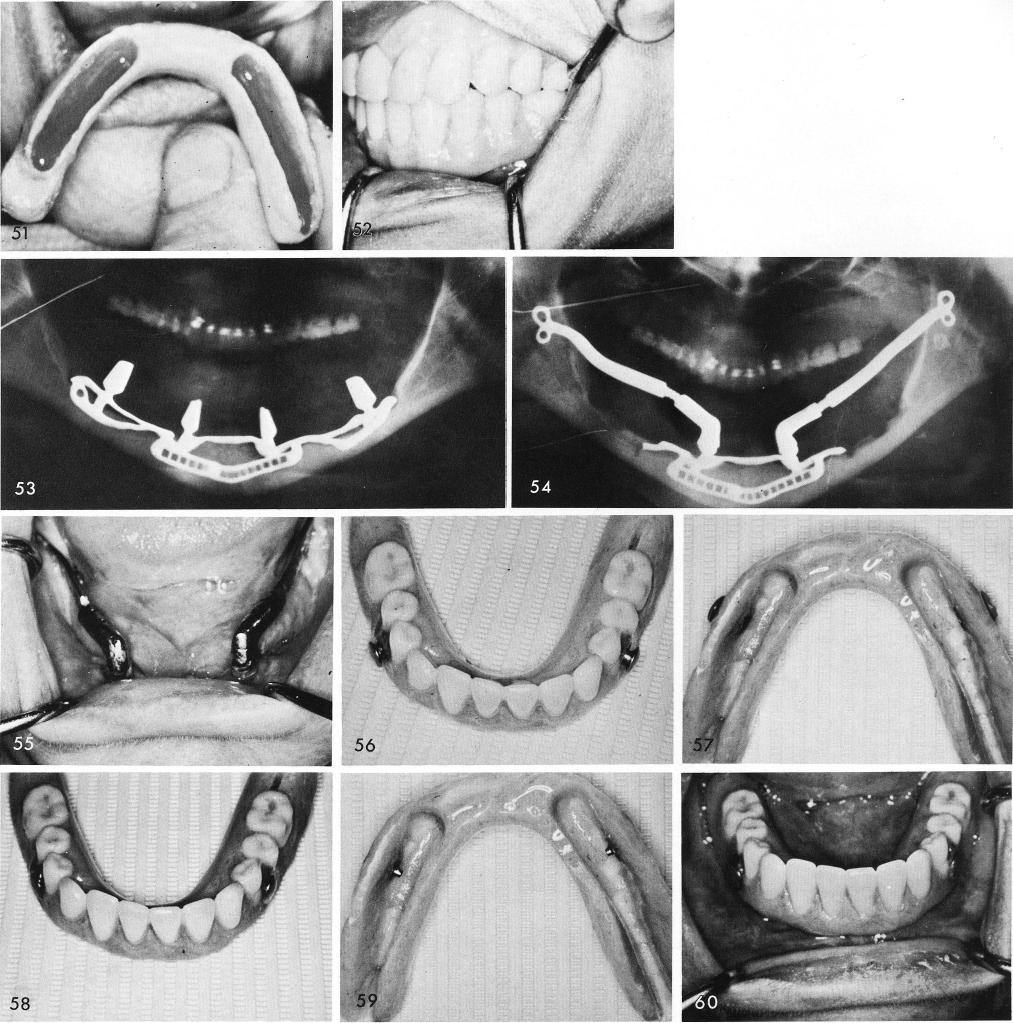

1 X ray showing final occlusion after implant and prosthesis placement